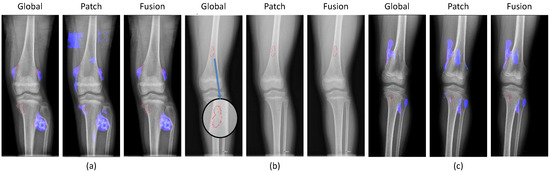

2.2.2. Global and Patch-Based Models

3.1. Experiments on Tumor Segmentation